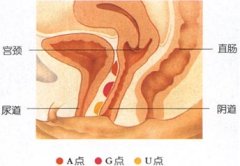

子宫颈是子宫下端的部分,其内腔呈圆筒形或梭形,称为宫颈管。它的上端为宫颈内口,下端为外口。宫颈管表面有一层粘膜,由于慢性炎症的长期刺激,使得颈管粘膜不断增生,堆积,并且从粘膜的基底层向宫颈的外口突出,从而形成了息肉。息肉的根部大多附着在宫颈管内或宫颈的外口,一般比较小,直径多在1厘米以下,单个或多个。也有较大者,直径可达数厘米,有蒂,随着生长而突出于宫颈口外。息肉小的,则仍留在宫颈管,仅微现于宫颈口。